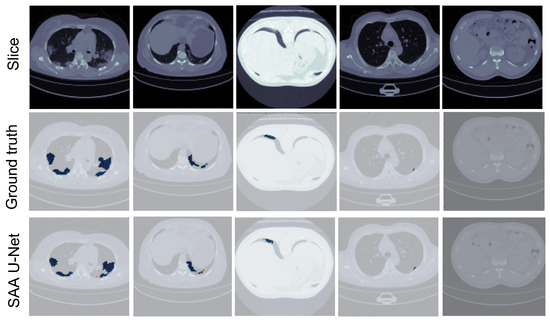

- SAA-UNet proved to be effective in segmenting the infection areas in CT images of COVID-19 patients.

- SAA-UNet showed good generalization when applied to different datasets.

6.2. Binary Class Classification

6.3. Multi-Class Classification